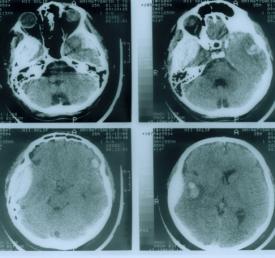

Наиболее информативным методом диагностики черепно-мозговой травмы является компьютерная рентгеновская томография, дающая представление о нарушениях анатомо-топографических соотношений в полости черепа. По изменению плотности тканей удается установить расположение, характер и степень ушибов мозга, выявить оболочечные и внутримозговые гематомы и гигромы, субарахноидальные и внутрижелудочковые кровоизлияния, отек мозга, а также расширение или сдавление желудочковой системы и цистерн основания мозга.

Окончательный диагноз ставят по результатам рентгенографии черепа в прямой и боковой проекциях (наличие повреждения костей), КТ и МРТ.